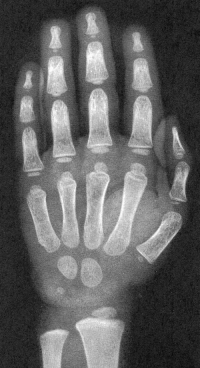

Sexo Masculino

2 anos

2 anos e 8 meses